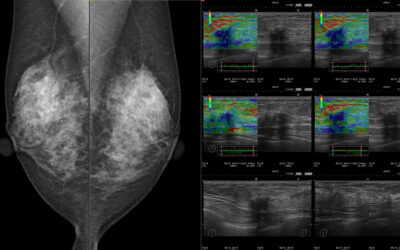

Medizinische Monitore erfüllen hohe Anforderungen

Herkömmliche Bildschirme für den Büro-Arbeitsplatz sind zur bildgebenden Befundung nicht geeignet und bergen Ungenauigkeiten bis hin zu verfälschten Ergebnissen. Mitunter ist die Nutzung handelsüblicher Bildschirme im medizinischen Bereich auch gar nicht erlaubt, wie...